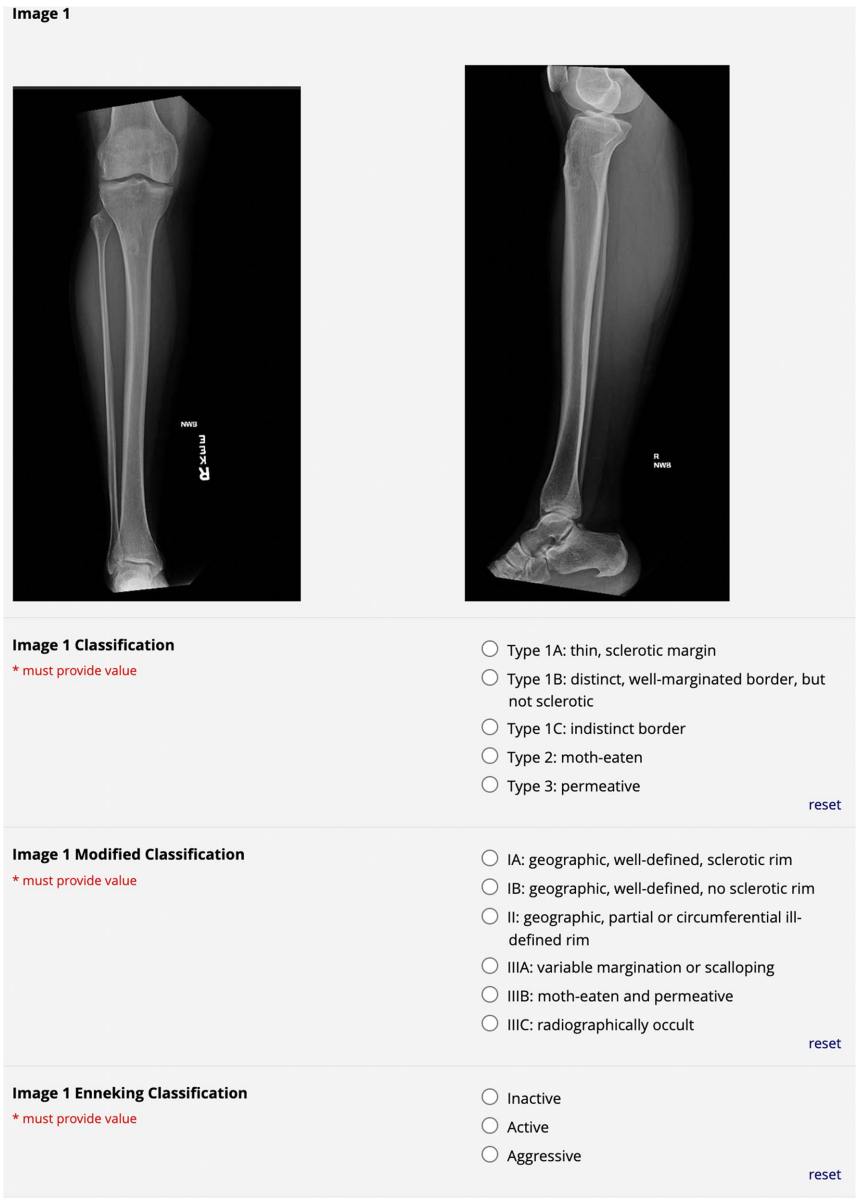

研究采用多阶段评估设计:首先通过Fleiss' kappa和Krippendorff's alpha统计量量化观察者间可靠性;其次用线性回归分析培训年限对分类一致性的影响;最后通过列联表计算各系统鉴别良恶性的准确性。所有评估均基于标准化的分类参考指南(如图1所示),确保评估过程规范统一。